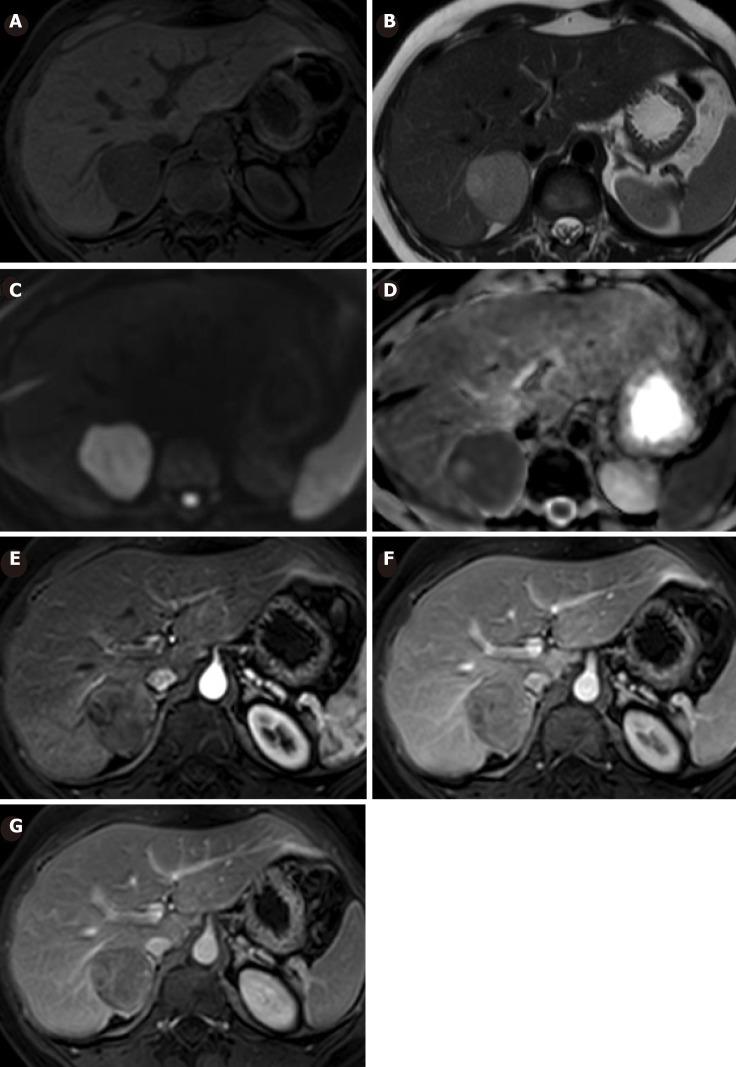

A 33-year-old female with a 10-year history of oral contraceptive use was diagnosed with a hepatic tumor as an incidental finding in an abdominal ultrasound. The patient showed no symptoms and physical examination was unremarkable. Laboratory functional tests were within normal limits and tests for serum tumor markers were negative. An abdominal magnetic resonance imaging (MRI) was performed, showing a 30 mm × 29 mm focal lesion in segment VI of the liver compatible with HCA or Focal Nodular Hyperplasia with atypical behavior. After a total of six years of follow-up, the patient underwent ovulation induction treatment for infertility. On a following MRI, a suspected malignancy was warned and hence, surgery was decided. The surgical specimen revealed malignant transformation of HCA towards trabecular hepatocarcinoma with dedifferentiated areas. There was non-evidence of tumor recurrence after three years of clinical and imaging follow-up.

一名有10年口服避孕药史的33岁女性,在腹部超声检查中偶然发现肝脏肿瘤。患者无症状,体格检查无异常。实验室功能检查在正常范围内,血清肿瘤标志物检测为阴性。进行了腹部磁共振成像(MRI)检查,显示肝脏VI段有一个30mm×29mm的局灶性病变,符合HCA或具有非典型表现的局灶性结节性增生。经过总共6年的随访,患者因不孕症接受了促排卵治疗。在随后的MRI检查中,发现疑似恶变,因此决定进行手术。手术标本显示HCA向小梁状肝细胞癌伴去分化区域恶变。经过3年的临床和影像学随访,未发现肿瘤复发迹象。